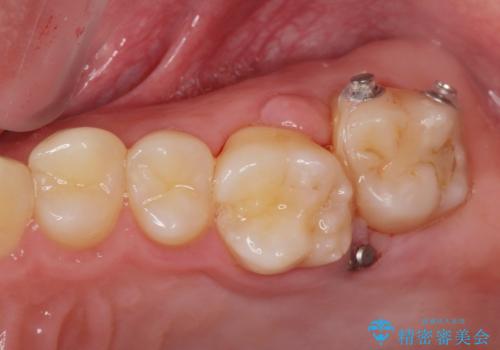

左上の奥歯がシザーバイトがありワイヤーで部分的な矯正を行い、シザーバイトを改善した後にインビザラインで全体的な矯正治療を行いました。

歯のがたつきが改善され大変満足されました。